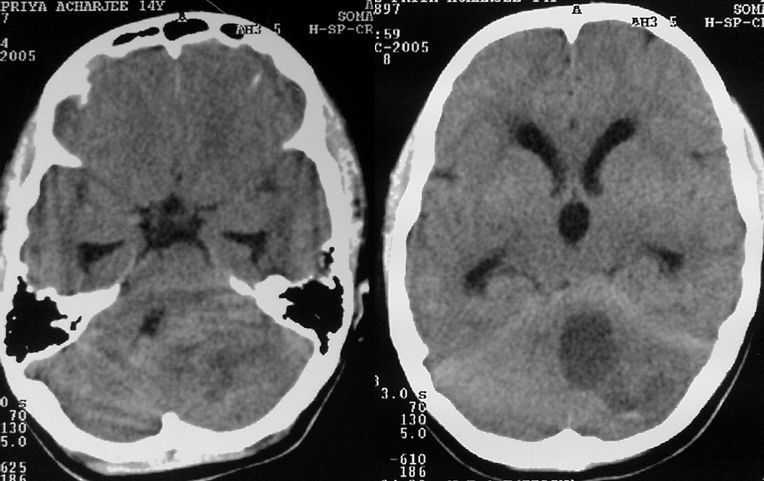

A cystic mass with mural enhancement in a child arising from the cerebellar hemisphere is usually a pilocytic astrocytoma. This patient went on to have a.

The 5-year survival rate is between 95-100or complete resection alone.  Cerebellar tumors are generally low-grade pilocytic, thus making complete  resection.